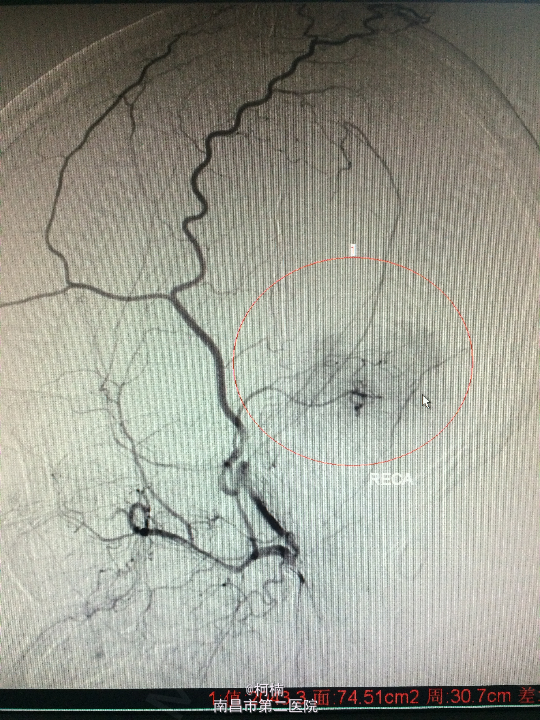

诊断:右侧小脑脑膜瘤 处理:先行介入栓塞肿瘤供血动脉,再行开颅手术治疗,术后予组织病理检查,提示:脑膜瘤